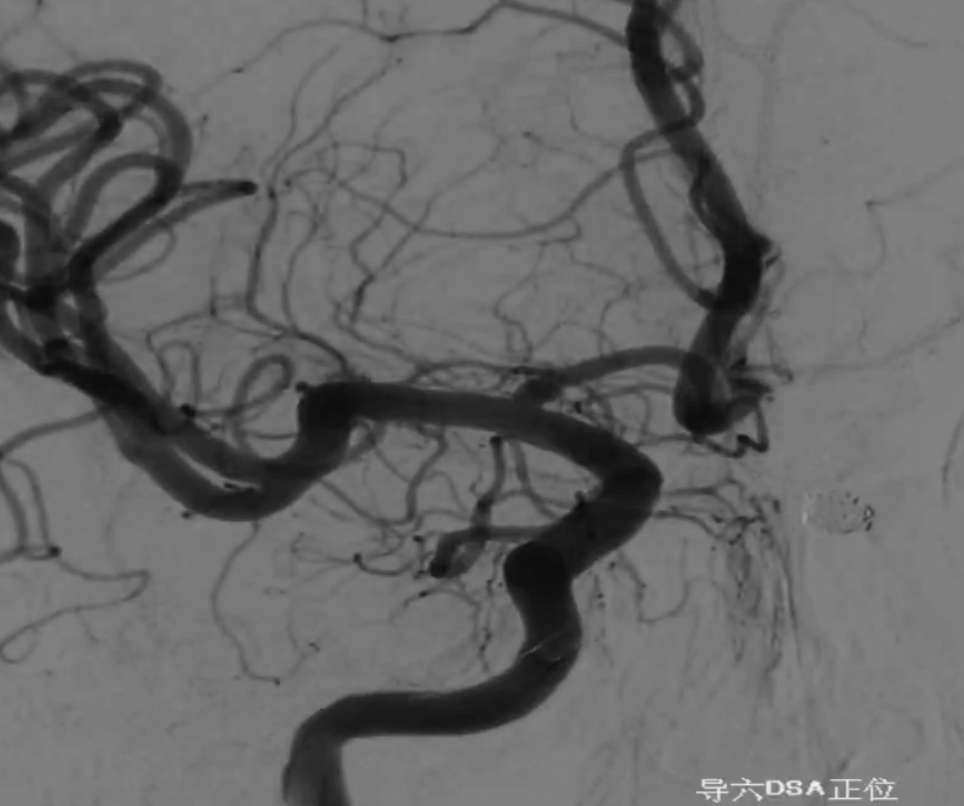

术前外院 DSA 2025-02

箭头所指右侧A1微小动脉瘤

工作位正位造影(图片)

工作位正位造影(视频)